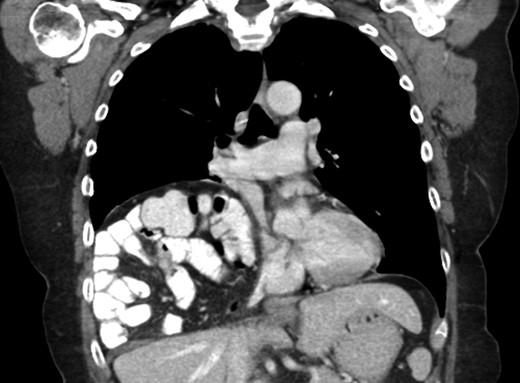

A 69-year-old female was referred to our clinic for an incidental finding of a large Morgagni hernia found on a recent CT chest scan for lung cancer screening. Patient reported occasional shortness of breath after prolonged ambulation but denied chest pain. She did have remote history of acid reflux symptoms but nothing recently. She denied issues with prematurity or issues with development as an infant, chest trauma, or MVA history. She did complain of occasional right shoulder pain but attributed this to arthritis. Denied history of heart attack, stroke, DVT, or PE. She had a 30-pack-year smoking history but quit a year prior. She was up-to-date on her colonoscopy, current within the past year. She denied hematochezia and melena, bowel habit changes or major body weight changes as well as any current abdominal pain. On examination her vitals were within normal parameters. Heart and lungs were unremarkable. Abdominal examination was soft with normal bowel sounds and nontender. Remainder of examination was unremarkable. Laboratory values included a normal CBC and BMP. A CT chest scan had demonstrated a large retroxyphoid hernia of Morgagni involving several loops of small bowel and transverse colon located in the right inferior hemithorax (Figs 1 and 2). No evidence of acute incarceration or strangulation were noted. A detailed discussion was undertaken with the patient regarding her hernia and she was consented for a laparoscopic repair with mesh.

Preoperative CT scan of chest demonstrating the wide retroxyphoid defect in the diaphragm with herniated small bowel and colon into the right inferior hemithorax.